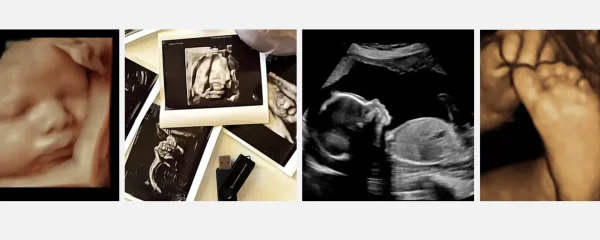

Pretecho

Je ziet je buik groeien, je voelt je baby vanaf een bepaald moment bewegen, maar je kan je baby pas zien als hij geboren is. Behalve op een pretecho dan. Soms wil je je kindje gewoon vaker zien dan medisch noodzakelijk is. Bijvoorbeeld, omdat je niet kunt wachten om te ontdekken wat het geslacht is van je kindje. Een pretecho is dan een prachtige keuze. Bel ons op het telefonisch spreekuur of vraag er naar tijdens je controle op het spreekuur en maak meteen een afspraak.

2D pretecho

Wil je graag een kwartiertje naar je baby kijken in 2D?  Dat kan ook bij ons op de praktijk.  Onze ervaren 13- en 20 weken echoscopisten maken de beste plaatjes van jullie kindje (afhankelijk van de ligging) en je krijgt de 3 mooiste foto's mee.

3D/4D uitgebreide echo

Wij hebben een mooie samenwerking met de Echopraktijk Dedemsvaart indien je graag ook na de echo geslachtsbepaling nog een keer een 3D/4D pretecho wil laten maken.  Aresh Mohamadi is naast echoscopist ook klinisch verloskundige in Zwolle en hij leidt echoscopisten op in Groningen. De allernieuwste echotechnieken zijn in huis om je kindje zo mooi en duidelijk mogelijk te kunnen laten zien.